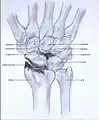

Stage I

Stage II

- Stage I: the osteoarthritis is only localized in the distal scaphoid and radial styloid.

- Stage II: the osteoarthritis is localized in the entire radioscaphoid joint.